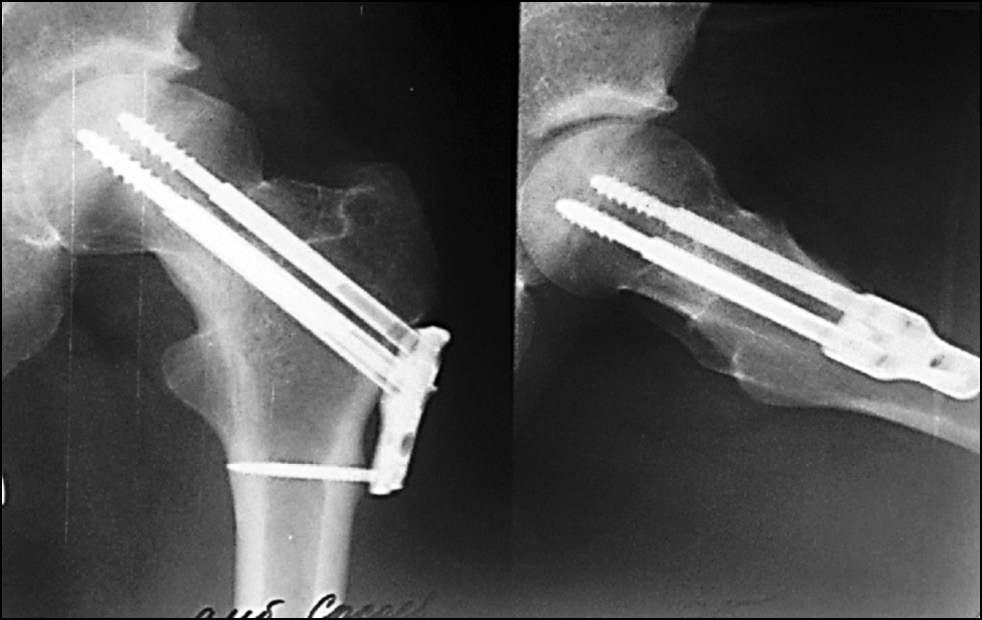

Следующий клинический пример демонстрирует достаточно редкий вид послеоперационного осложнения для группы исследования — миграцию металлофиксатора. Пациентка Н., № и/б 7124/2019, 50 лет, поступила в клинику через 1,5 часа после дорожно-транспортного происшествия с изолированным переломом ШБК справа, тип Garden III (рис. 5).

Рис. 5. Рентгенография тазобедренного сустава пациентки Н. при поступлении.

Fig. 5. X-ray of the hip joint of patient N. upon admission.

Учитывая возраст пациентки (50 лет), от эндопротезирования ТБС было решено воздержаться. Через 18 часов с момента получения травмы была выполнена операция методом ДДФ с использованием 4 телескопических винтов в ШБК (рис. 6).

Рис. 6. Рентгенография тазобедренного сустава пациентки Н. после операции.

Fig. 6. X-ray of the hip joint of patient N. after surgery.

Пациентка была обучена ходьбе с дозированной нагрузкой на оперированную конечность до 35% от массы тела. На 5-е сутки пребывания в стационаре была выписана на амбулаторное лечение. На контрольные консультации и этапную рентгенографию после операции пациентка не приходила. Через 4 месяца с момента операции в связи с появившимися болями в области послеоперационного рубца пациентка обратилась в клинику. Факт повторной травмы категорически отрицает, при детальном сборе анамнеза выяснено, что через 2 недели с момента операции пациентка самостоятельно отказалась от костылей, ходила с полной нагрузкой на оперированную конечность. При выполнении контрольной рентгенографии ТБС через 6 месяцев с момента операции диагностирована миграция телескопического винта кнаружи, линия перелома ШБК прослеживается (рис. 7a).

Рис. 7. Рентгенография тазобедренного сустава пациентки Н. с миграцией телескопического винта: a — через 6 месяцев с момента операции, b — после удаления мигрировавшего винта.

Fig. 7. X-ray of the hip joint of patient N. with migration of the telescopic screw: a — 6 months after the operation, b — after removal of the migrated screw.

Ввиду наличия миграции фиксатора и прослеживающейся линии перелома на рентгенограмме пациентке предложено оперативное вмешательство — эндопротезирование ТБС. От предложенной операции больная категорически отказалась, настаивая на удалении мигрировавшего компонента металлоконструкции, что и было выполнено через 6 месяцев с момента операции (рис. 7b).

После удаления винта пациентка, несмотря на рекомендации дозирования нагрузки на оперированную конечность, продолжала ходить без дополнительной опоры. Через 6 месяцев с момента получения перелома ШБК при контрольной рентгенографии костей таза (рис. 8) обнаружена консолидация перелома. Пациентка ходит без дополнительной опоры и без хромоты, симптом Транделенбурга отрицательный. Оценка качества жизни пациентки, рассчитанная с использованием опросника SF-36, соответствовала хорошему функциональному результату (физический компонент здоровья — 28,5 балла, психологический — 29,1 балла). Показатель по шкале Харриса составил 90 баллов и был оценён как отличный функциональный результат.

Рис. 8. Рентгенография костей таза пациентки Н. через 6 месяцев с момента перелома шейки бедренной кости.

Fig. 8. X-ray of the pelvic bones of patient N. 6 months after the fracture of the femoral neck.